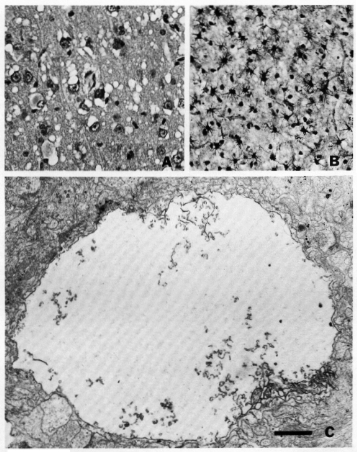

Ag 1A—Spongiform degeneration of cerebral cortex in experimental kuru. (H&E, x 400). B—Astrocytic hypertrophy in the cerebral cortex in Creutzfeldt-Jakob disease. (Cajal’s gold sublimate, x 200). C—Dilated nerve cell process containing curled membrane fragments in experimental kuru. (Line = 1 sm). Photographs from Marsh9 and published with permission of Academic Press.